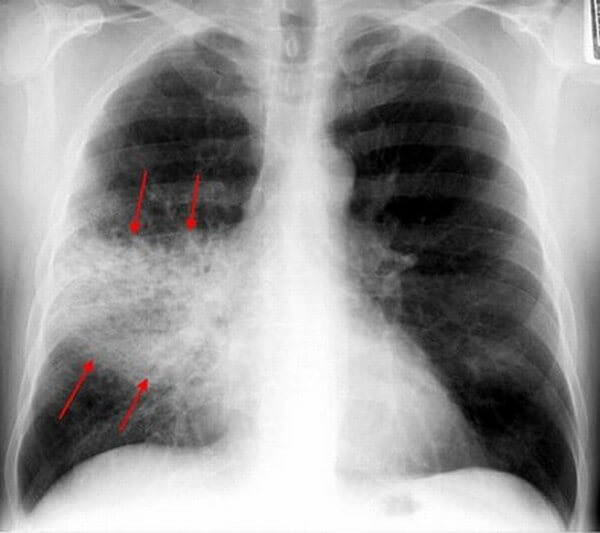

При абсцедирующей пневмонии на снимке отчетливо видно тотальное затемнение области инфильтрации и уплотнение плевры; наблюдаются полости до 2 см, в которых скапливается гнойная жидкость.

Фотоснимок при абсцедирующей пневмонии

- Абсцедирующая пневмония. Проявляется обширным затемнением пораженной области, признаками утолщения плевры и наличием полостей разного размера, наполненных жидкостью.